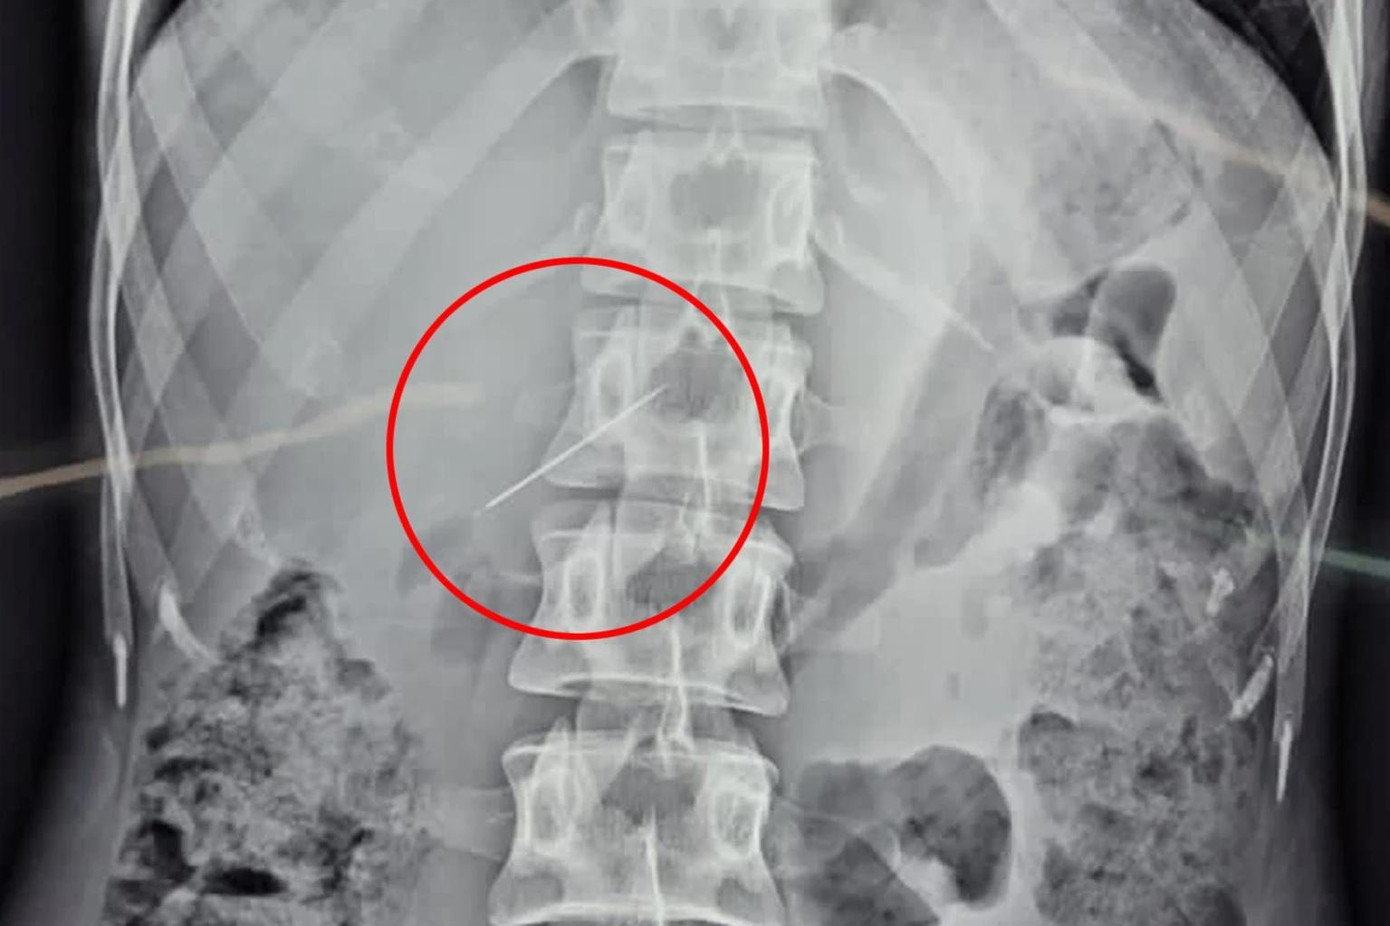

| Chiếc kim khâu vô tình lọt vào cơ thể người phụ nữ và được các bác sỹ mổ nội soi lấy ra. |

Sau 10 ngày trải qua nhiều cuộc kiểm tra, bao gồm siêu âm, nội soi, chụp X-quang và CT, bản siêu âm cuối cùng đã phát hiện một chiếc kim nhỏ mắc kẹt trong gan bệnh nhân.

Ngay khi phát hiện ra cây kim, các bác sỹ đã khẩn trương tiến hành phẫu thuật để lấy dị vật ra. Jam Press đưa tin, phẫu thuật rút kim kéo dài hai giờ bằng phương pháp nội soi.